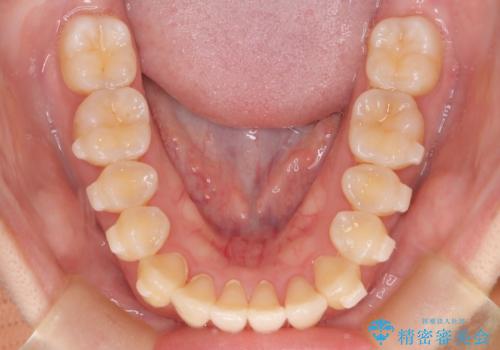

【インビザライン】反対咬合を治したい

- 前歯の反対咬合を主訴に来院されました。

インビザラインにて歯列弓の拡大により叢生の改善を行うことができ、患者様にも満足していただました。